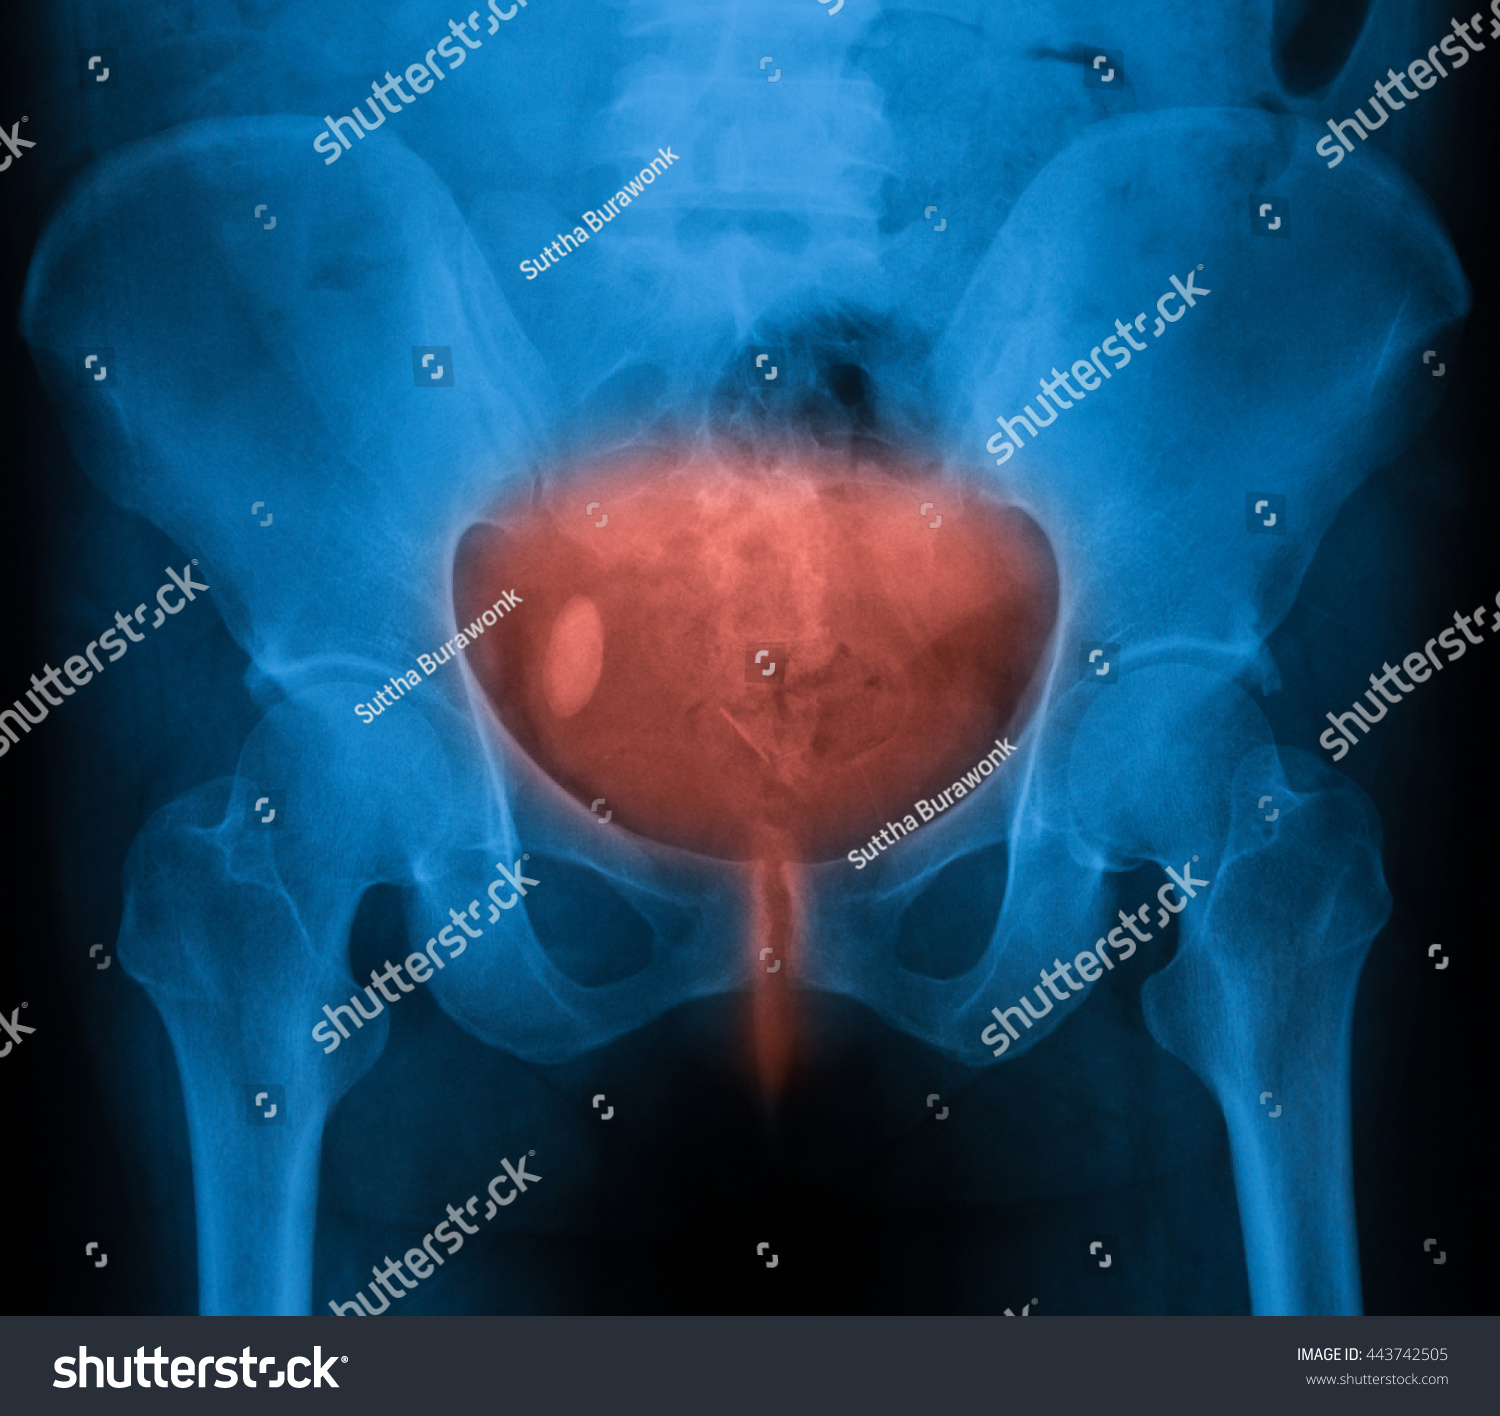

Xray Image Bladder Showing Urinary Bladder Stock Photo 443742505 …

X-ray of urinary bladder taken on 14 May 2007 shows several vesical …

X-ray of urinary bladder taken on 14 May 2007 shows sev | Open-i

Case number: 2. X-ray of urinary bladder, taken on 11 June 2010, showed …